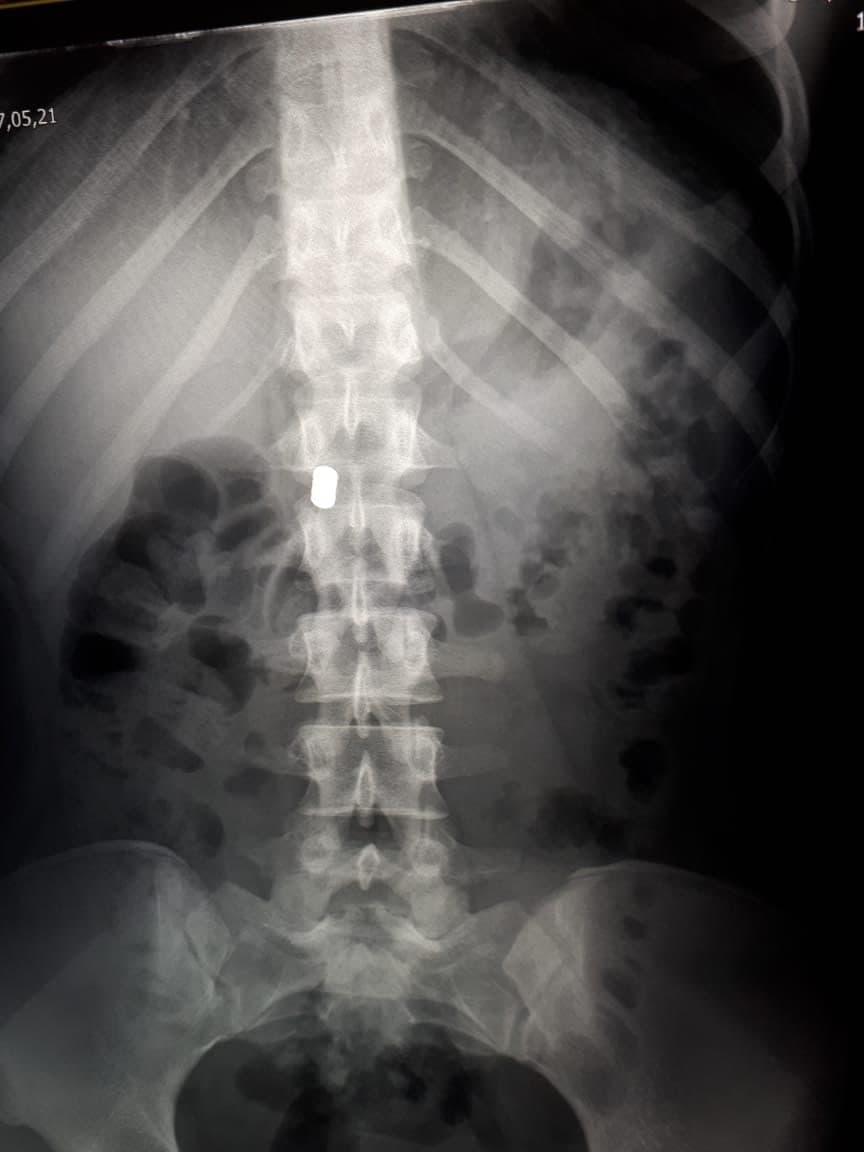

Как сообщили в облздраве, девочка обратилась в больницу с жалобами на боли в животе 16 мая. Врачи выполнили рентгенографическое исследование брюшной полости, в ходе чего обнаружили инородные предметы.

«Два магнитных цилиндра находились в желудке, два — в двенадцатиперстной кишке. Они уже начали продавливать стенки, что привело бы к перфорации кишечника. Еще сутки, и мог возникнуть перитонит, который обернулся бы тяжелыми последствиями для здоровья ребенка», — рассказал главный врач больницы Андрей Караваев.